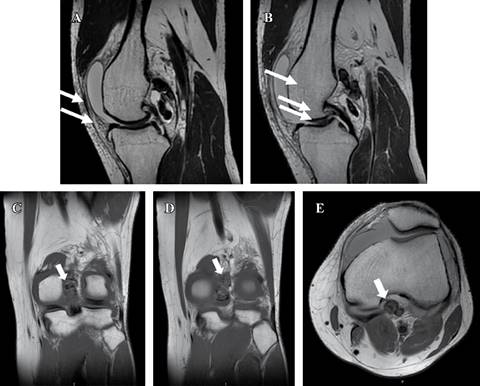

En radiografías anteroposterior (AP) y lateral de rodilla, no se encontraron datos patológicos, por lo que se decidió la realización de una resonancia magnética (RM) simple, en la cual, además de lesión grado I en menisco medial y ligamento cruzado anterior (LCA), se identificó entre la cápsula posterior y el ligamento cruzado posterior al menos cuatro imágenes ovoides, con bordes bien definidos y comportamiento heterogéneo, predominantemente hiperintenso en secuencia de densidad protónica con supresión grasa (Proton Density Fat-supressed Sequence: PD-FS), hipointenso en T1 y T2 y sin señal en la secuencia de susceptibilidad magnética, con un tamaño aproximado de 7 a 20 mm (Figura 1). Se descartó el uso de ultrasonido por tener disponibilidad inmediata de RM.

Figura 1: Resonancia magnética simple de rodilla izquierda. A y B) Corte sagital en secuencia T2. C y D) Corte coronal en secuencia T1. E) Corte transversal en secuencia T1. Se observan imágenes ovoides entre la cápsula posterior y el ligamento cruzado posterior (flechas blancas), bien delimitadas, de 7 a 20 mm, hipointensas y sin señal en susceptibilidad magnética, sugestivas de tumor tenosinovial de células gigantes.